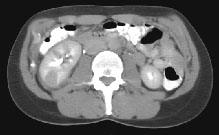

Fig.1 Fig.2 Fig.3

HELICAL CT FINDINGS: The CT was performed on AIC’s multi-slice helical CT (MSCT) scanner. Images with 5 mm collimation were obtained before, immediately following and 5-10 minutes after power injection of IV contrast. The region of the appendix was unremarkable. However, the right kidney and perinephric region were abnormal. Fig. 1 and Fig. 2 illustrate patchy and wedge-shaped low attenuation areas in the right kidney, and Fig. 3 shows stranding/infiltration of perinephric fat around the lower pole consistent with inflammatory changes (arrows).

DIAGNOSIS: The CT images are most compatible with acute pyelonephritis (APN) even without any laboratory results. Shortly after, results of blood work and urinalysis revealed leukocytosis and pyuria substantiating the CT diagnosis.